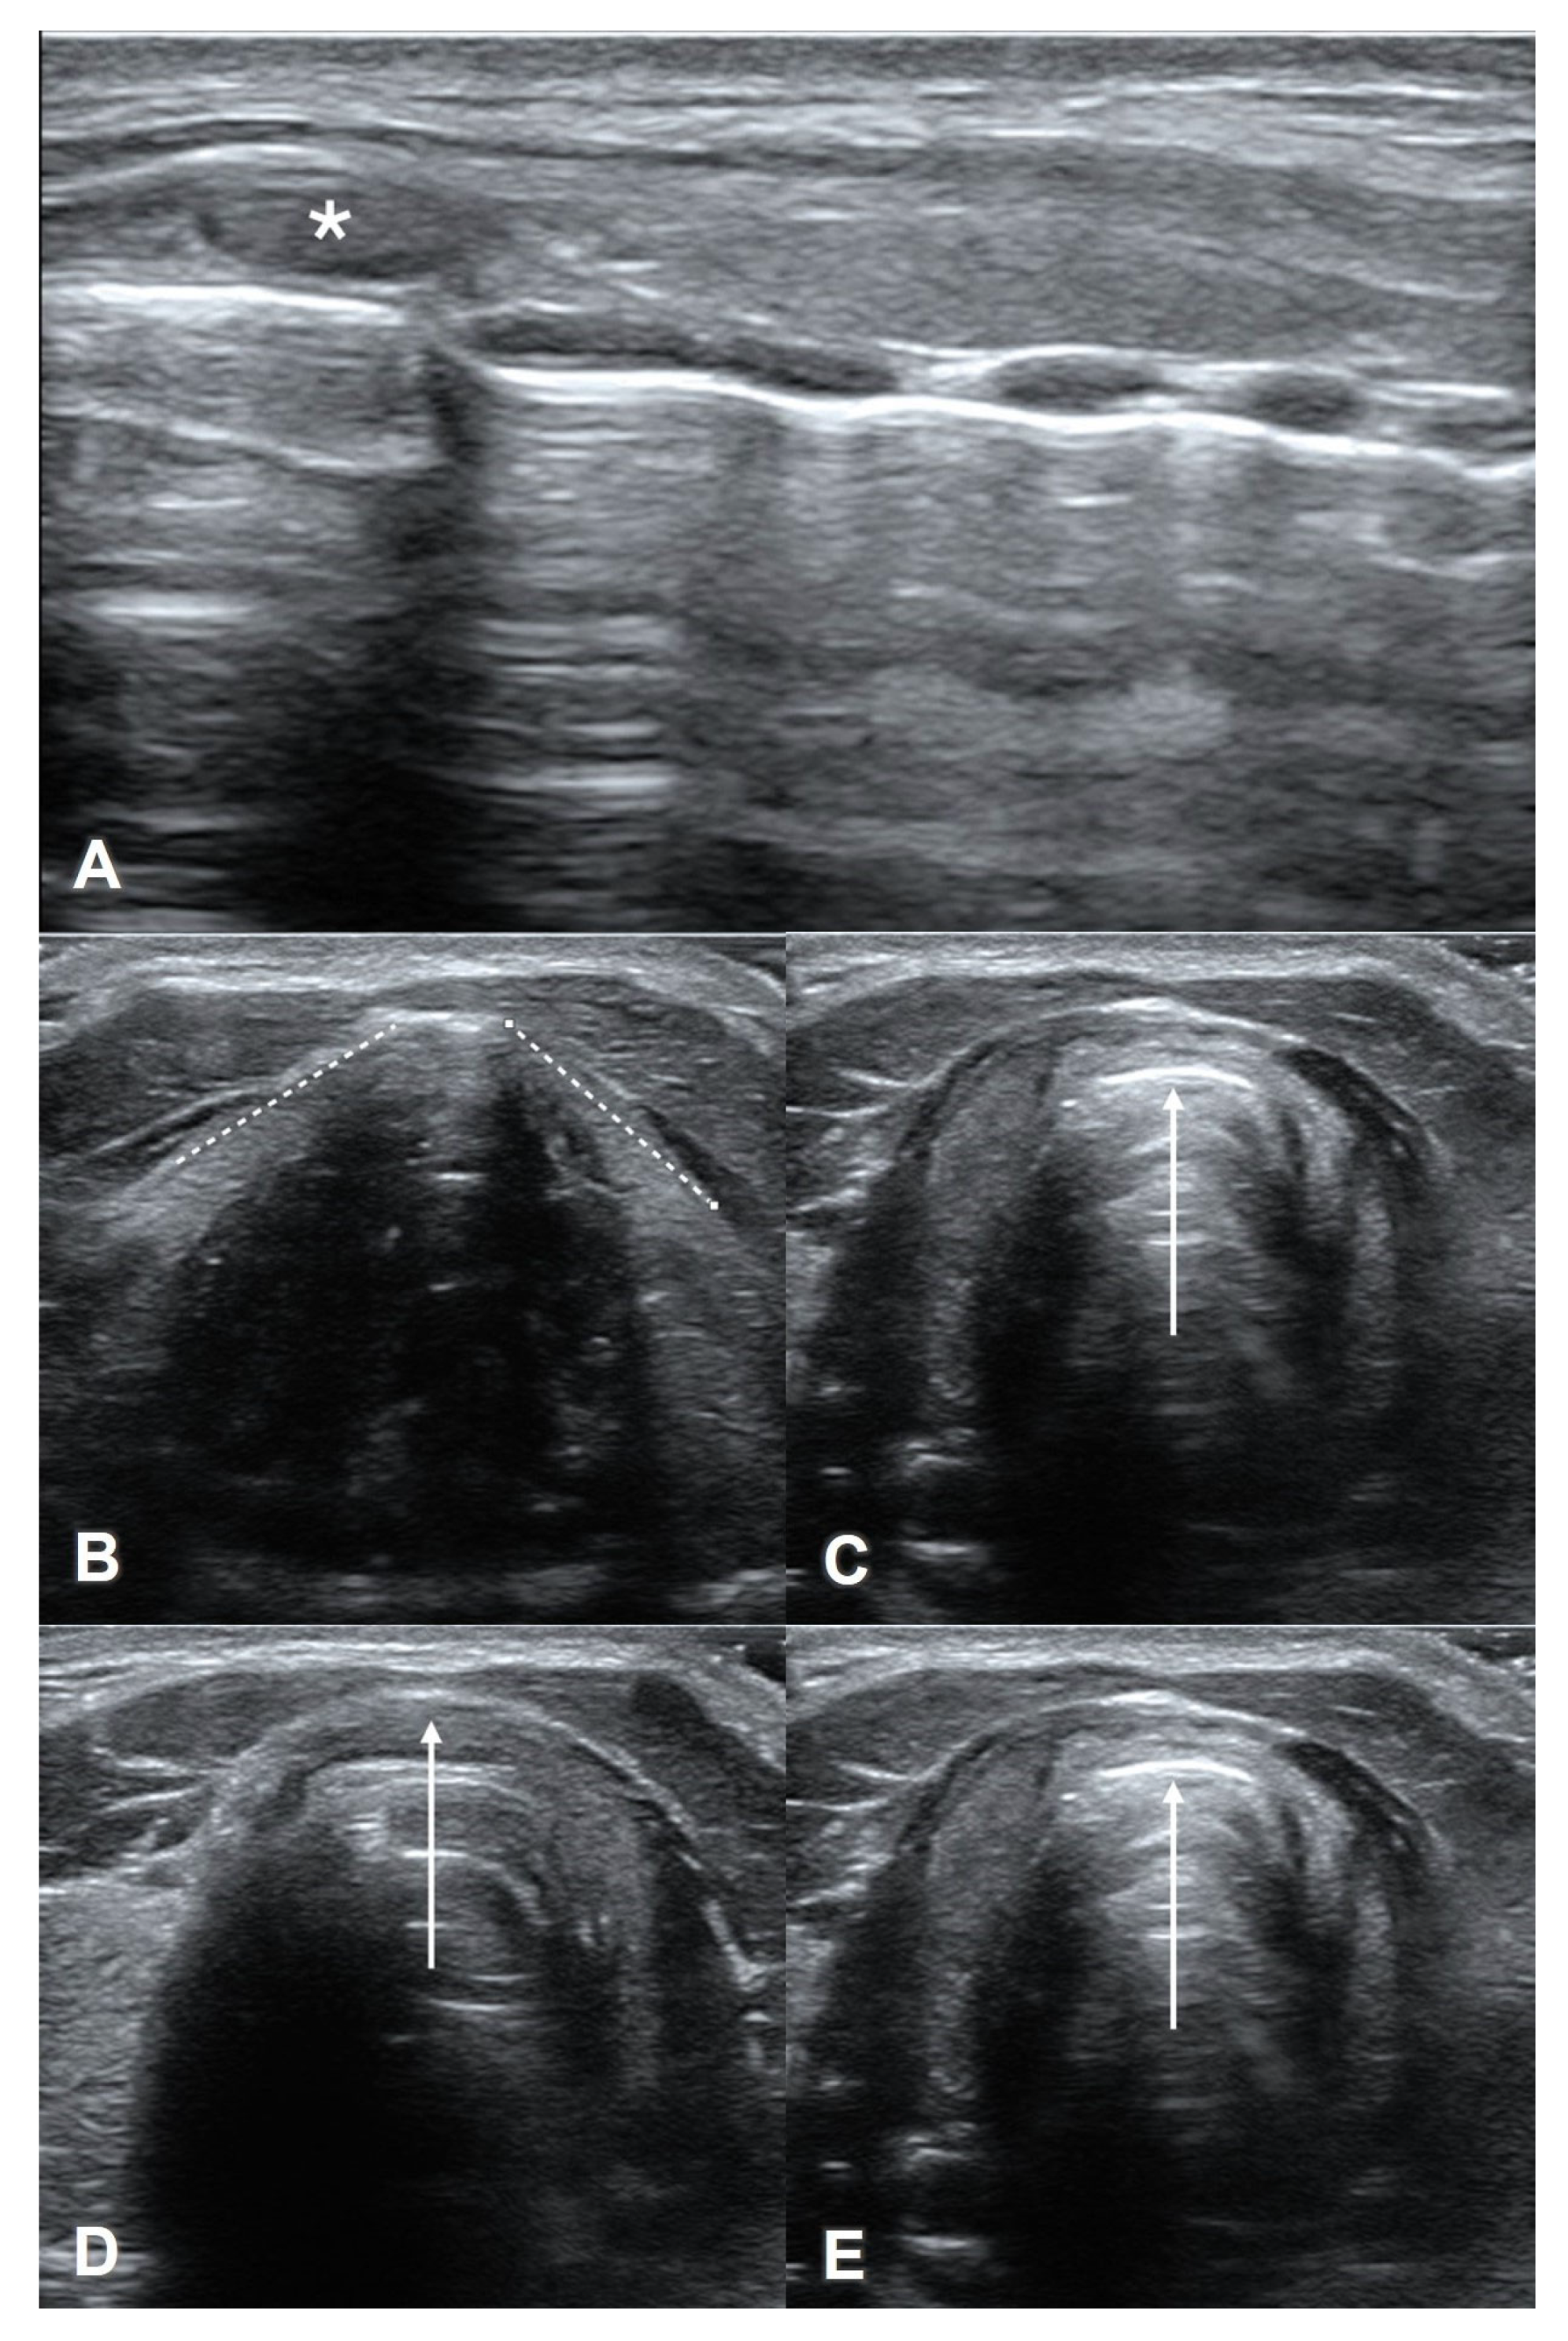

3. Probe Selection and Technique

4. Upper Airway Sono-Anatomy

4.1. Suprahyoid View

4.2. Thyrohyoid View

4.3. Thyroid View

4.4. Cricothyroid View

4.5. Suprasternal View

7. Assessment of Laryngeal Edema